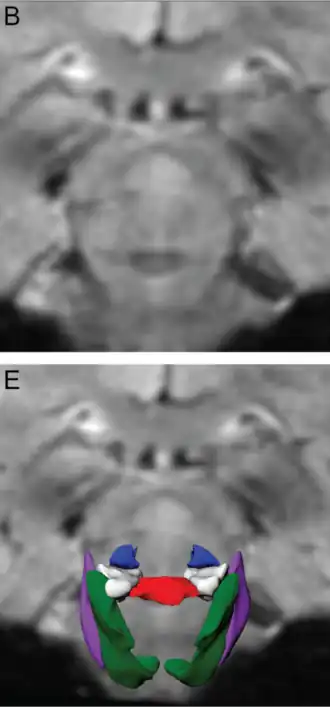

El núcleo pedunculopontino (PPN por sus siglas en inglés, de pedunculopontine nucleus) o núcleo tegmental pedunculopontino (PPT o PPTg),[1] es un conjunto de neuronas situado en la parte superior de la protuberancia del tronco encefálico,[2][3] caudal a la sustancia negra y adyacente al pedúnculo cerebeloso superior. Tiene dos divisiones de subnúcleos: la pars compacta, que contiene principalmente neuronas colinérgicas, y la pars dissipata, que contiene principalmente neuronas glutamatérgicas y algunas neuronas no colinérgicas.[3] El núcleo pedunculopontino es uno de los principales componentes del sistema activador reticular.[4][5]